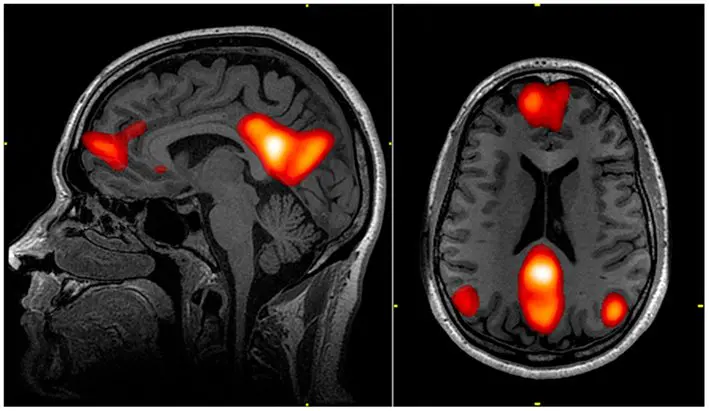

Researchers have also used resting-state fMRIs to look at how different parts of the brain communicate. They found that highly creative people have stronger connections between the left inferior frontal gyrus (the brain’s control center) and the default mode network, which is linked to imagination and mind-wandering. In other words, creative people show stronger communication between the regions involved in control and imagination (6).

Scientists at Pennsylvania State University have also studied how the brain’s default mode network (DMN) activates when the mind isn’t focused on outside stimuli, like when you’re about to fall asleep (7). The DMN plays a major role in creativity, and some researchers believe it may directly drive creative thinking (8).